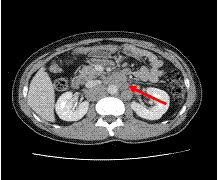

고환암의 후복막림프절 전이 여부를 확인하는 가장 정확한 방법으로 고환절제술 후 고환암의 병기 결정에 이용됩니다. 특히 항암화학요법에 대한 반응여부 등을 판정하기 위하여 시행됩니다.

[고환암의 전이로 인한 대동맥과 대정맥 주위의 후복막림프절의 종대가 관찰되는 CT 소견]